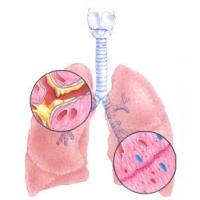

Симптомы диффузного пневмосклероза специфические. Так, изначально человек чувствует исключительно отдышку. На первых порах она появляется при физической нагрузке, а в дальнейшем и в состоянии покоя. Кожные покровы человека становятся цианотичного оттенка. Происходит это из-за снижения вентиляции альвеолярной ткани легких.

Самым характерным признаком является симптом пальцев Гиппократа. Они меняют форму и становятся похожими на барабанные палочки. Диффузный пневмосклероз сопровождается явлениями хронического бронхита. Пациентов начинает беспокоить кашель, который в первое время затяжной, а в дальнейшем навязчивый.

Утяжеляет течение пневмосклероза основное заболевание. Это может быть хроническая пневмония или бронхоэктатическая болезнь. Возможно, появление ноющей боли в груди, слабость, повышенная утомляемость и похудание. В некоторых случаях развиваются признаки цирроза легкого. Это грубая деформация грудной клетки, атрофия межреберных мышц, смещение сердца, крупных сосудов и трахеи в сторону поражения. Диффузный пневмосклероз сопровождается гипертензией малого круга кровообращения и симптомы легочного сердца.

Симптомы болезни очень специфичные. У большинства людей болезнь протекает скрыто. Однако с течением времени у больного может появиться одышка. Она возникает после изнурительных тренировок. Кроме того, диффузный пневмосклероз проявляет себя изменением цвета кожи. Обычно кожный покров приобретает цианотичный оттенок. Помимо одышки и изменения цвета кожных покровов, при развитии недуга появляются следующие признаки:

- Симптом пальцев Гиппократа. У больного меняется форма пальцев.

- Кашель. С течением времени он приобретает хронический характер.

- Ноющая боль в области грудной клетки. Такой признак появляется лишь в том случае, если диффузный пневмосклероз возникает на фоне хронической пневмонии.

- Упадок сил. Этот симптом возникает практически во всех случаях.

В редких случаях на фоне диффузного пневмосклероза возникают признаки цирроза легких. У пациента может деформироваться грудная клетка или атрофироваться межреберные мышцы. В тяжелых случаях сердце и крупные кровеносные сосуды начинают смещаться.